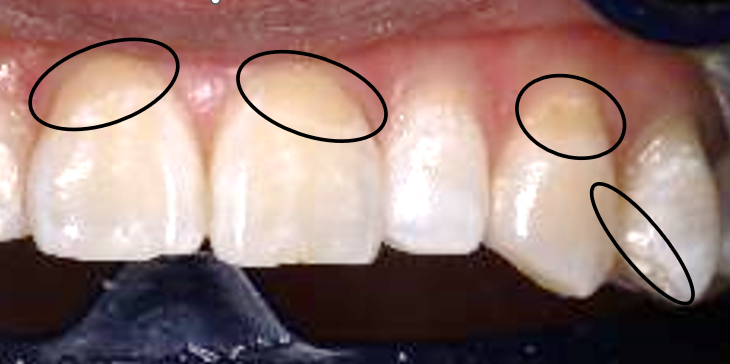

医院で撮影してもらった、術前術後写真です!

左端の色調サンプルを見ていただくと、色味が「A3」から「A1」レベルに2段階上がったのが見えるかな?と思います😊

私も一部詰め物が入っているのですが、その部分は白くならず、ちょっと黄色浮きしちゃいました💦

また、お気づきかもしれませんが、私は体質的に元々歯に色ムラがあります(>_<)

この色ムラはホワイトニングをしても治りません⚠️

色ムラがあるまま白くなるのです!